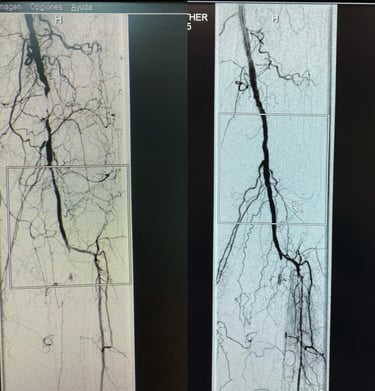

Angioplastía Arterial